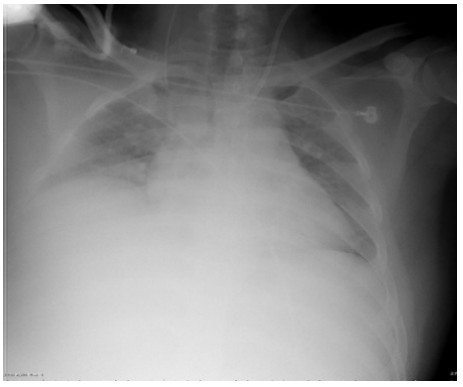

SAP发生呼吸衰竭的原因很复杂,其原因有以下几种。(1)SAP因为炎症反应导致的ARDS(图 1),这是普遍认为的一种原因,但实际上ARDS在SAP患者呼吸衰竭中很多时候是非主要原因。SAP急性期虽然病情进展很快,出现多脏器功能损伤,甚至休克,有类似于脓毒症和感染性休克样的表现,但其炎症反应并不如脓毒症这么强烈,大量的研究可见SAP发生过程其IL-6很少过千,而脓毒症则IL-6动辄大于5 000或10 000,SAP两肺影像学也很少有典型的非心源性肺水肿的双侧阴影,超声下也很少有“B线”表现。但胆道感染引起的脓毒症合并SAP的患者,其ARDS发生率会明显上升。现在随着高脂血症胰腺炎的增加,部分患者到院时同时存在糖代谢障碍,合并有糖尿病酮症,入院前后出现糖尿病酮症昏迷,有些患者会伴有呕吐误吸或者插管时误吸,这类患者在急性期会出现误吸相关的ARDS。(2)SAP是腹腔重症的一种,急性期因为腹膜后急性胰周液体积聚和急性胰周坏死物积聚,导致腹腔压力进行性升高,随之出现横膈抬高,两肺压缩,从而导致“小肺”,这和ARDS的“baby lung(小肺)”不同(图 1: ARDS;图 2、3: 腹内压14 mmHg和23 mmHg的对比,明显看到图 3呈现横膈抬高引起的小肺)。因横膈位置上抬导致小肺是SAP呼吸衰竭的主要原因。(3)两下肺不张(图 4)和胸腔积液(图 5):这两个原因也是导致SAP呼吸衰竭的主要原因,因为膈下刺激,导致两下肺的不张和大量胸腔积液常见于SAP患者,这两种原因导致的呼吸衰竭也和ARDS不同。(4)其他原因:胸腔出血、肺梗死和气胸亦可见于SAP相关呼吸衰竭,但相对少见。

| 图 2 腹内压14 mmHg |

| 图 3 腹内压23 mmHg |